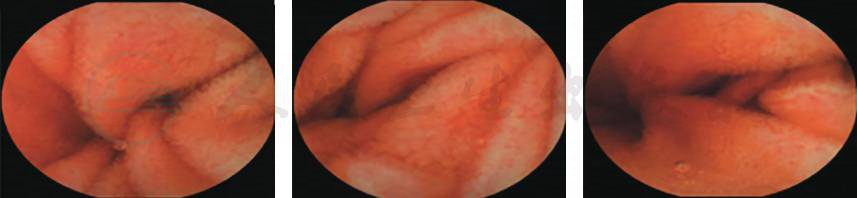

患者症状好转,复查胃镜示慢性糜烂性胃炎、十二指肠球炎(图2)。

图2 电子胃镜下表现

胶囊内镜报告(图5):胶囊内镜顺利通过食管进入胃腔,见胃黏膜散在充血糜烂,未见活动性出血;胶囊通过幽门口进入小肠,十二指肠黏膜见散在充血糜烂;胶囊通过部分小肠区域时缓慢。胶囊内镜全程视频9h,胶囊拍摄视频显示未进入大肠,结合患者病情分析,不能排除胶囊在小肠内滞留可能。

图5 胶囊内镜表现